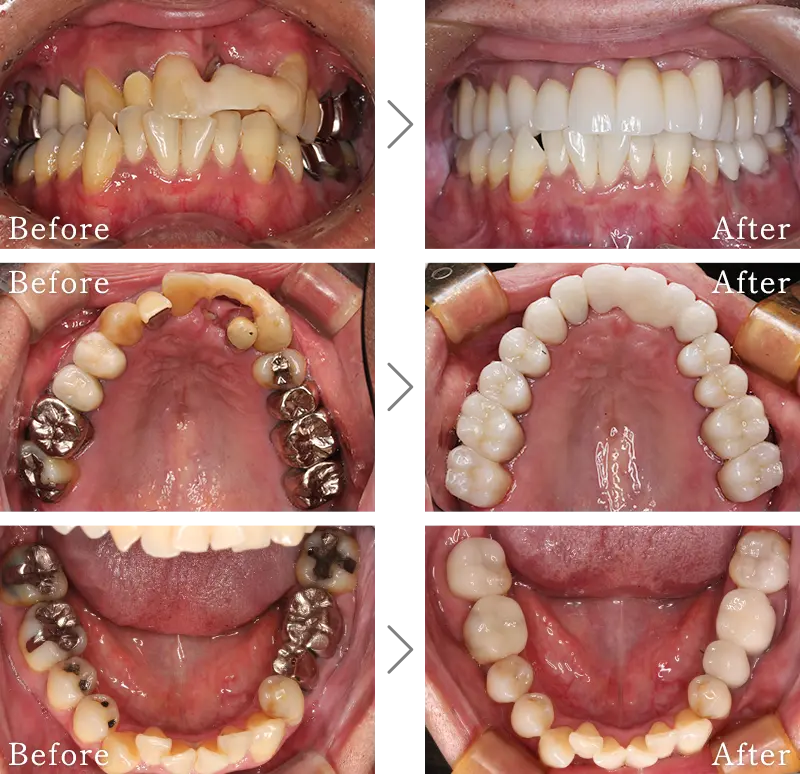

セラミック治療は、本物の歯のように白く自然な透明感のある「セラミック」という素材を用いて行う治療です。虫歯の治療で歯を削った後は、金属(いわゆる銀歯)で補う方法が一般的ですが、白い歯とかけ離れた見た目に不満を持たれる方を多いと思います。

セラミックは見た目の美しさはさることながら、硬さも天然の歯に近く、機能面でも申し分ありません。

セラミックは、豊富な色調と特有の透明感があり天然歯と色調を合わせることができます。また、保険適応のプラスチック素材と違い、セラミックは物性が化学的に安定しているので、しっかりメインテナンスすれば長年使用していても変形や変色はほぼありません。